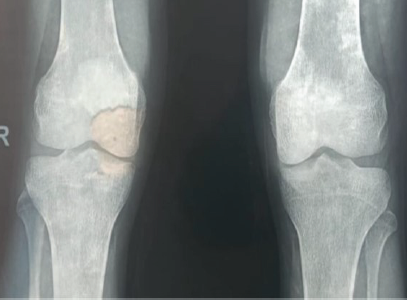

Simultaneous TKA and Revision of Post-ORIF Patellar Non-union with Bone Grafting: A Case Report

Hiroko Sakamoto , Masaki Nagashima , Ryo Sasaki , Kentaro Tanaka , Mitsuru Yagi

………………………………p.157-162